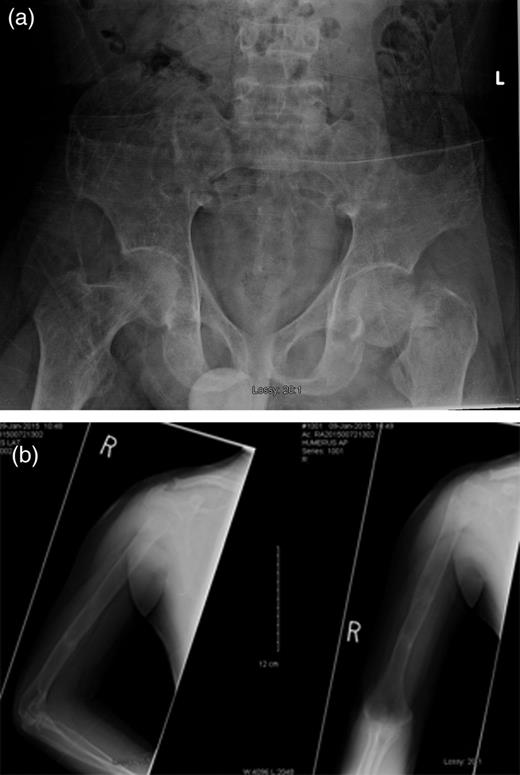

One day after sustaining this injury, the patient underwent an uncemented left total hip arthroplasty (THA) (Fig. 2), and acetabular fixation was supplemented with multiple screws, and he maintained touch-down weight bearing for 6 weeks postoperatively. His right humeral fracture was managed conservatively using a functional brace. A parathyroidectomy was performed 2 days later. The histopathology report confirmed the diagnosis of a parathyroid adenoma. Within 3 days postoperatively, the PTH level had decreased to 4.9 pmol/l, and the calcium level had returned to normal at 2.42 mmol/l. The calcium level continued to fall, and 2 weeks after the parathyroidectomy, it had reached 1.70 mmol/l. After a further 20 days, it started to normalize and then continued to remain stable, as shown in Fig. 3.